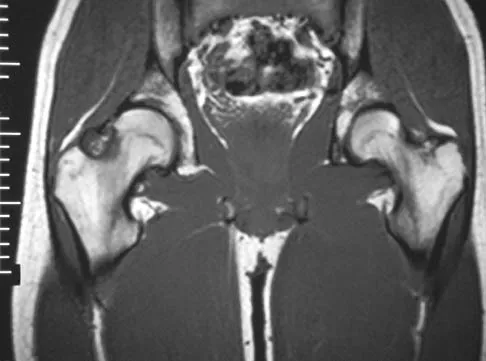

A 35-year-old patient has right hip pain. Figures 34a and 34b show the coronal MRI scan and the biopsy specimen. What is the most likely diagnosis?

Explanation

Alcohol abuse, steroids, Caisson disease, sickle cell disease, and radiation therapy are the leading causes of nontraumatic osteonecrosis of the femoral head. Arlet J: Nontraumatic avascular necrosis of the femoral head: Past, present, and future. Clin Orthop 1992;277:12-21.